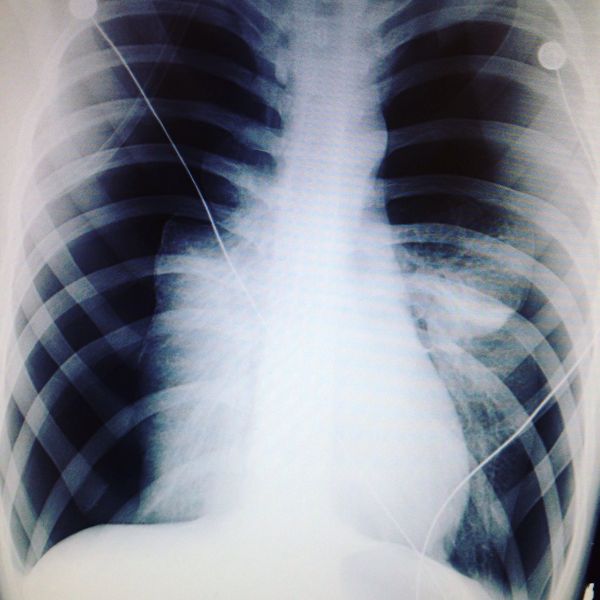

30dwc 3rd October 2004 This is an x-ray of my chest that day. Both my lungs collapsed to a very dangerous level - the small white parts either side of my spine are my lungs, the black space in the rest of the image is the pneumothorax. It really did nearly kill me. Thankfully,